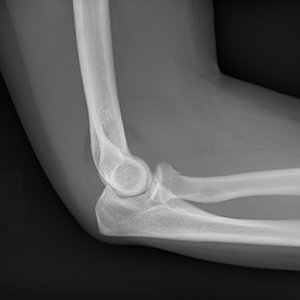

FractSure is coming soon: A second opinion on X‑ray fractures, powered by AI. Designed for parents, patients, and peace of mind.

Whether it’s a suspected fracture or something that just doesn’t feel right, FractSure™ is your second set of (digital) eyes.

FractSure™ uses advanced AI to review X‑ray images and look for signs of broken bones. FractSure has been trained on emergency data from all over the world.

FractSure™ is built on technology already trusted by hospitals around the world. While no tool is perfect, FractSure is designed to spot even small fractures with a high degree of accuracy.